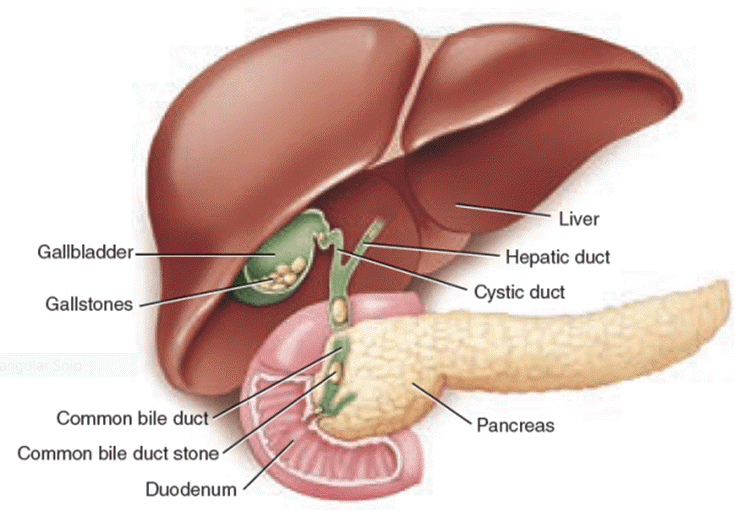

Анатомия и особенности Гартманова кармана желчного пузыря